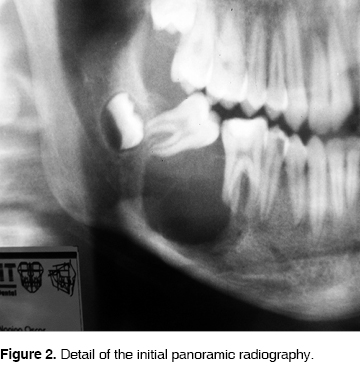

A 14 year old boy was admitted to the dental clinic at the Hospital Juárez de México in July 2004, with a right mandibular tumor like lesion, of apparently 7 months of evolution. The patient reported tenderness and there was no other relevant history for this lesion. The swelling was located from the right second premolar to the third molar zone with vestibular expansion with displacement and mobility of the first and second molar ipsilateral (Figure 1). The panoramic radiograph showed a unilocular radiolucid lesion that extended from the first and second right molars with a very close relation to the third molar, well defined borders and measuring approximately 30 x 20 mm, producing displacement of the teeth involved (Figure 2). The simple CT scan showed a lesion that produced vestibular and lingual cortical slimming and expansion with preservation of the mandibular border (Figure 3).